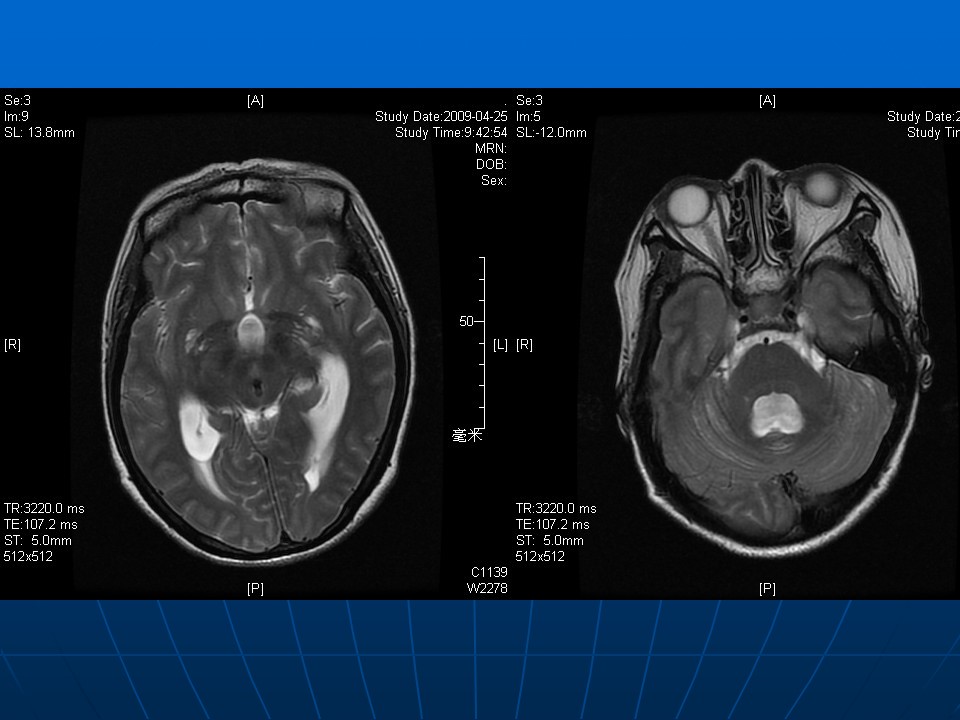

脑卒中的康复治疗PPT

脑卒中的康复治疗PPT脑卒中: 是一组急性脑血管疾病。是指突然发生的、由脑血管病变引起的局限性脑功能障碍,并持续时间超过24小时或引起死亡的临床症候群(WHO)分类:缺血性卒中(Ischemic Stroke): 又称脑梗死,包括脑血栓形成,脑栓塞和短暂性脑缺血发作(TIA)出血性卒中(Hemorr...